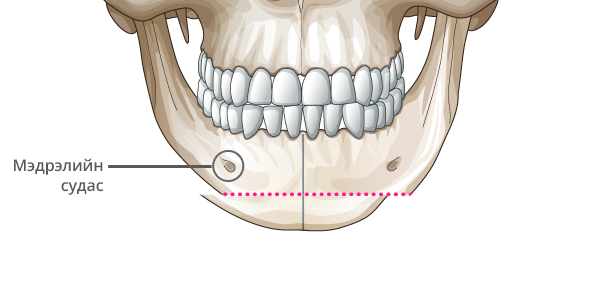

Step 2

Эрүүний гол хэсгийг зүсэлт хийж авна.